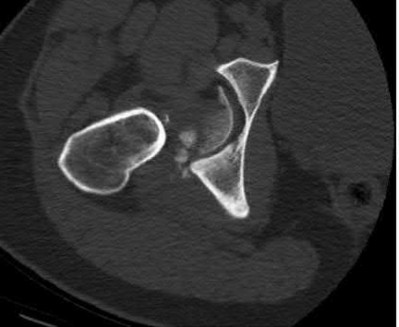

Question 2

A 28-year-old male sustains a severe hyper-dorsiflexion injury to his ankle in a motor vehicle accident, resulting in a Hawkins Type III talar neck fracture. Which of the following arteries provides the predominant blood supply to the body of the talus, placing it at significant risk for avascular necrosis in this injury?

Explanation

The artery of the tarsal canal, which is a branch of the posterior tibial artery, provides the dominant blood supply to the talar body. In a Hawkins Type III fracture (talar neck fracture with subtalar and tibiotalar dislocation), the blood supply from the artery of the tarsal canal, the artery of the sinus tarsi, and capsular vessels are disrupted, leading to an avascular necrosis (AVN) rate approaching 100%.